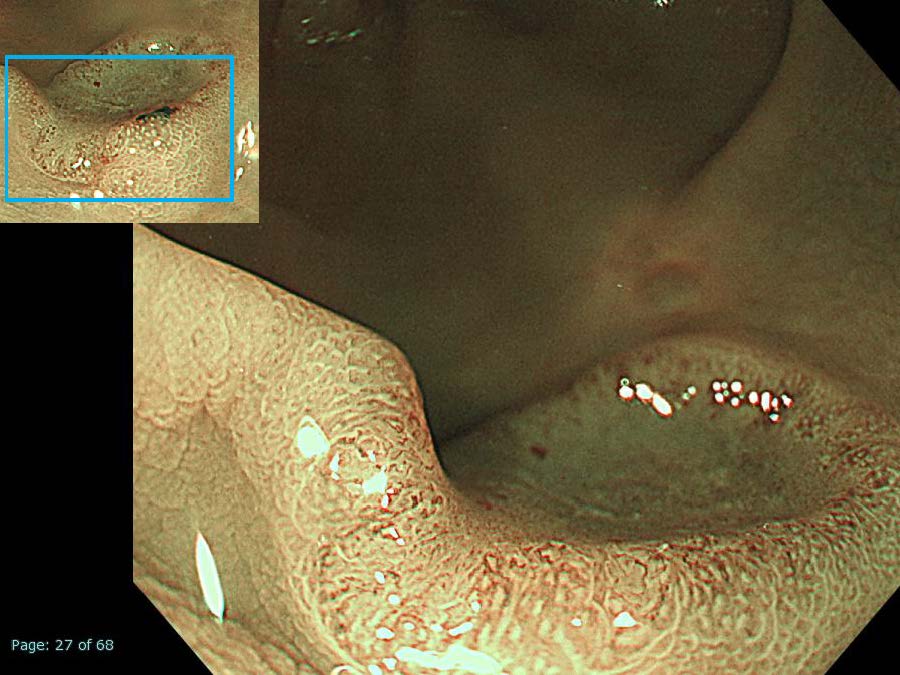

消化管Mapping~大腸~ 2021.10.27

消化管Mapping

消化管Mapping~大腸~

消化器内科

内視鏡検査・治療